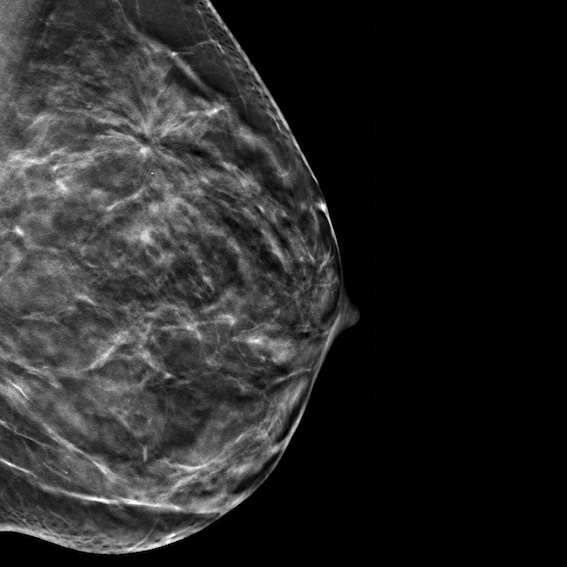

Get Screened